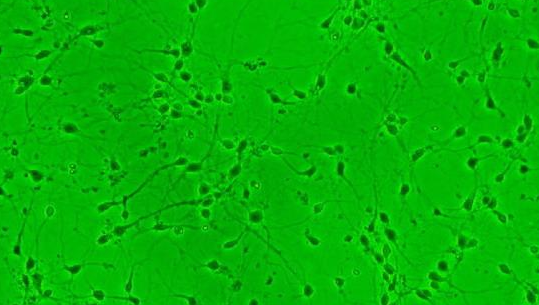

细胞名称:NCI-H2107 人小细胞肺癌

形 态:贴壁;上皮细胞样

NCI-H2107细胞提供原代/传代细胞,质量保证,生长状态良好,没有细菌 真菌 支原体等微生物污染。细胞一般以T25培养瓶包装,容积75ml细胞数量可达10的6次方左右。购买方收到细胞应当马上检查,如发现细胞状态不佳或者大部分死亡情况下,须当天联系我司。得到我技术确认后免费补发一株。一周内发现细胞有污染情况,请拍照记录并与销售部联系。

文献和实验都是贴壁细胞,在消化传代过程中,步骤如下:倒尽旧的培养液->用无血清的培养基清洗一两次->加入一定量的胰酶,置于37度培养箱中5--10分钟,使细胞悬浮->显微镜下观察,待细胞大部分变圆时,回到超静台->加入一定量的含血清的新培养液,以终止胰酶作用->反复吹打细胞->再置显微镜下观察,直到细胞全部悬浮起来->吸出一部分加入新的培养瓶中->最后再补充加入一定量新的培养液。注意: 1、吹细胞时尽量多吹边角儿,此处细胞生长的多。2、吸出细胞前要混匀,可以剧烈震荡培养瓶。3、我们用的是DMEM